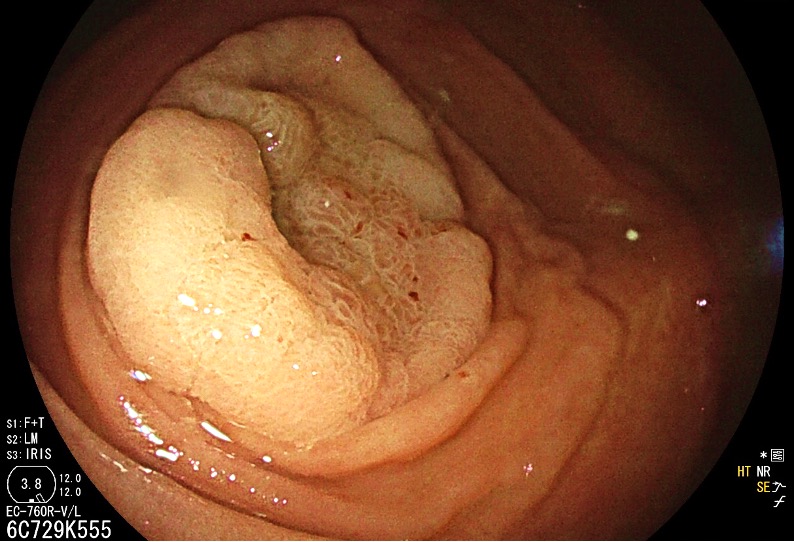

Hybrid endoscopic full-thickness resection of an appendicular laterally spreading tumour - 2.º Classificado (Fotografia)

Maria Manuela Estevinho, Jaime Rodrigues, Rolando Pinho, Edgar Afecto, João Correia, Teresa Freitas

Centro Hospitalar Vila Nova de Gaia/Espinho - Serviço de Gastrenterologia

A 69-year-old woman, with no relevant medical history, was referred to our department after identification, in screening colonoscopy, of a laterally spreading tumour, granular homogenous, with 30mm, centred in the appendiceal orifice. The peripheral portion of the lesion was removed by piecemeal mucosal resection, while endoscopic full-thickness resection (EFTR, Ovesco Endoscopy) was performed on the central portion invading the appendix. Follow-up was uneventful. The EFTR specimen contained the transected appendix; histological analysis showed a tubulovillous adenoma with low-grade dysplasia. EFTR is a minimally invasive alternative to resect appendiceal lesions; this hybrid approach enables exceeding the size limit of the device.